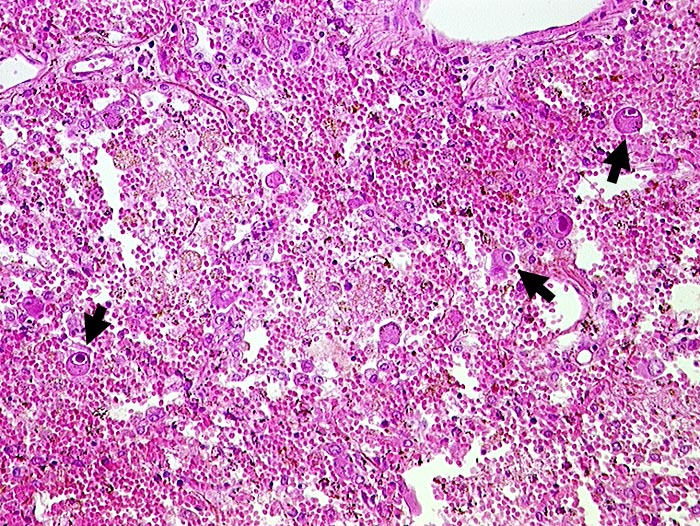

CMV-Infekt:

Das Zytomegalievirus befällt Makrophagen und Endothelzellen von immunsupprimierten Patienten. Die virusbefallenen Zellen sind deutlich vergrössert und enthalten einen grossen intranukleären Einschlusskörper, der sich durch einen schmalen hellen Zytoplasmasaum von der Kernmembran abhebt (Eulenaugenzellen). Die bis zu 1 Mikrometer grossen zytoplasmatischen Einschlusskörper konzentrieren sich meist im paranukleären Zytoplasma. Der Ausstrichhintergrund in der BAL ist oft sauber, da aufgrund der Immunsuppression eine entzündliche Reaktion fehlt.